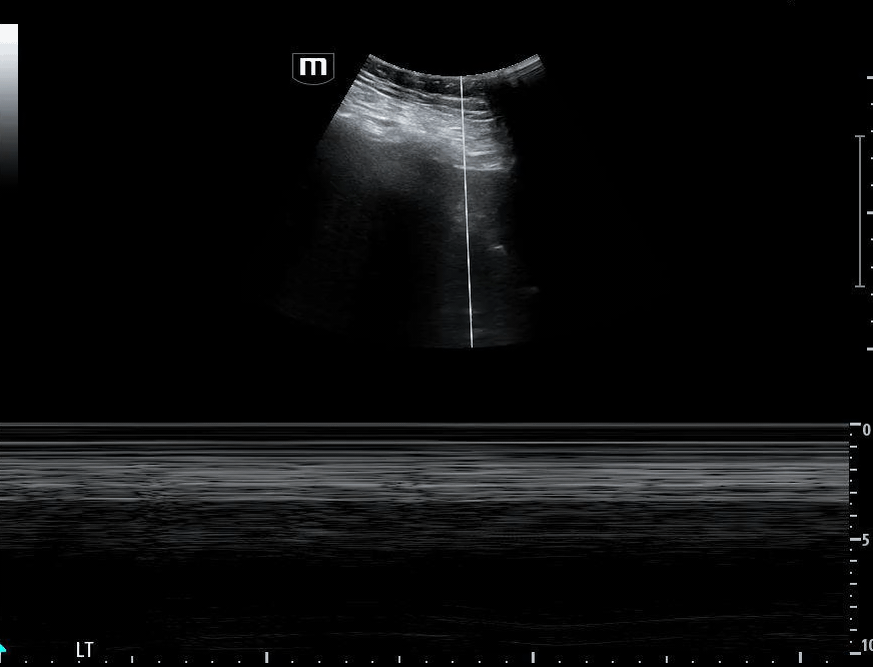

Additional ultrasound imaging are obtained:

Image 5 shows a subxiphoid cardiac view

Image 6 demonstrates a plethoric inferior vena cava (IVC), concerning for elevated intrathoracic pressure and impaired venous return.